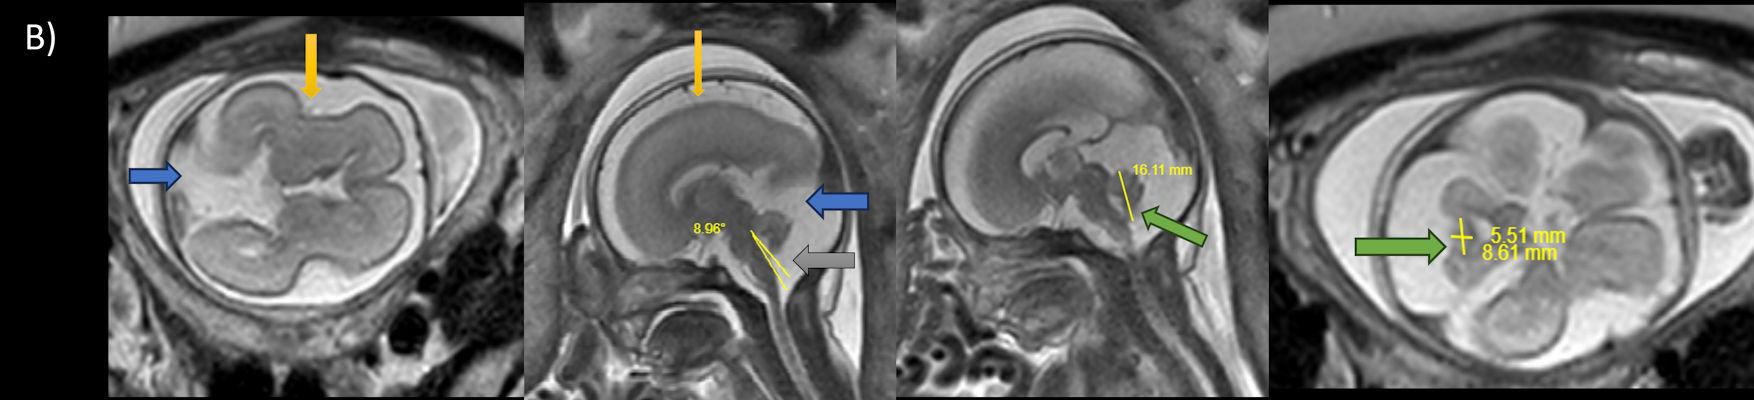

- A) USG incelemede serebral kortikal yapılar düzleşmiş (ok), gyrus sayısı azalmıştır (ok). Kalın ve ekojenik korteks mevcut olup korteks -beyaz cevher ayrımı silik görünümdedir. Posterior fossada ekstraaksiyel BOS mesafesi artmış görünümdedir (ok).

- B) Aksiyel ve sagittal T2A görüntülerde gyrus ve sulkuslarda azalma mevcut olup korteks kalınlaşmış görünümde ve operkulizasyon ayırt edilememiştir. Korteks beyaz cevher ayrımı zor seçilmektedir (ok) Ekstraaksiyel BOS mesafesi artmış görünümdedir (ok). Yapılan ölçümlerde; tegmentovermian açı :8 derece (ok) serebellar vermis boyutları kraniokaudal: 16 mm, aksiyel: 5,5×8,5 mm (ok) ölçülmüş olup BPD:27w ile uyumlu olan fetüste haftasıyla uygun olarak değerlendirilmiştir.

- Gri/beyaz cevher oranı beyaz cevher aleyhine azalmıştır.

- Operkulizasyon yokluğuna bağlı sylvian fissürün açık görünümü ve vertikal yerleşimi karakteristik bir bulgudur. Serebral yapılar; sığ ve vertikal yerleşimli sylvian fissür sebebiyle “8” görünümündedir. Ancak bu görünümün 26. gestasyonel haftaya kadar normal olduğu akılda tutulmalıdır.

- İnsula açıkta olup klastrum ve eksternal kapsül bulunmayabilir. Beynin gross görünümü fetüste sulkusların oluşmaya başladığı 20. gestasyonel haftayla benzer görünümdedir.

- Dandy Walker Malformasyonu(DWM); posterior fossa ve serebellar vermiş gelişim bozukluğudur. Radyolojik incelemelerde vermisin hipoplazi/aplazisi, tentoryum serebellide superiora yer değiştirme , tegmentovermian açının 45 derecenin üstünde olması ile tanı konur. İntrauterin dönemde bu açı sınırı fetüs gestasyonel haftasına göre değişkenlik göstermektedir.